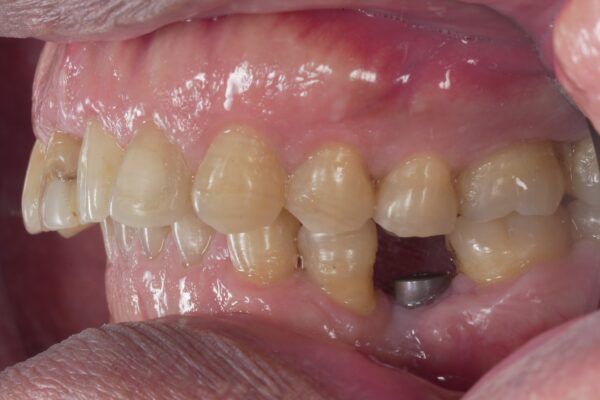

Thank you Ivan and Jedediah for your reply. I have proceeded with impression scan. This is the photo of the implant. Implant was still firm and asymptomatic upon removal of healing abutment.

Great to hear @Williamwy1994 ! It looks good to me. No need to worry. Actually a high five is in order!